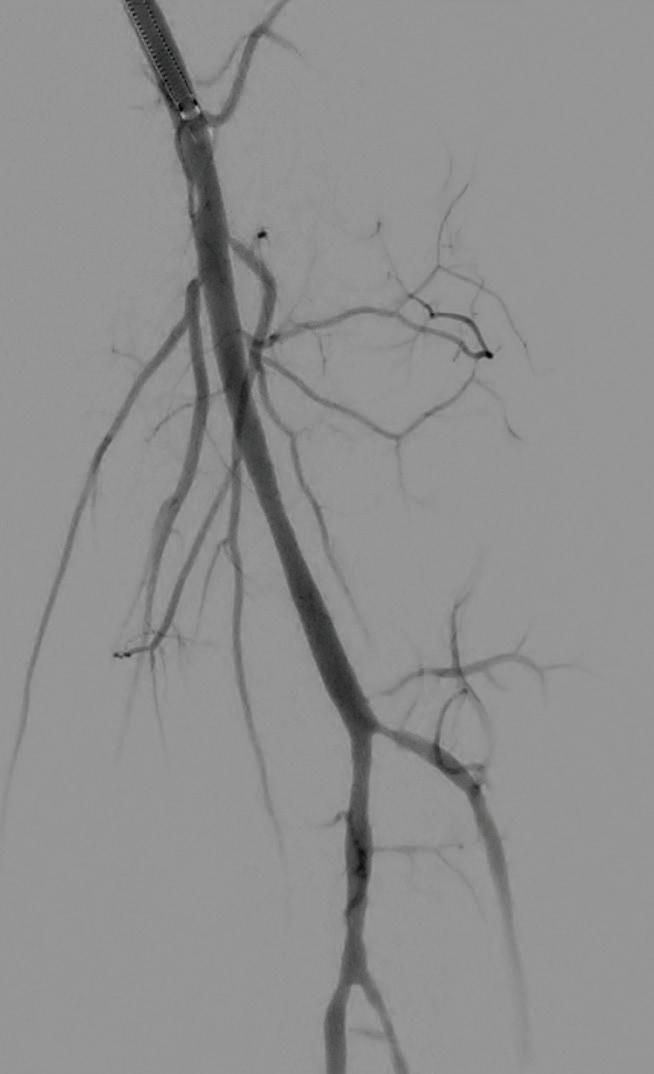

Shockwave E8 3mm x 80mm to the posterior tibial artery

The posterior tibial artery was successfully crossed first. The long-length posterior tibial artery disease was treated with a Shockwave E8 3.0mm x 80mm IVL catheter, with no pre-dilatation required. A total of 200 pulses were delivered along the length of the posterior tibial artery (Figure 3).

Shockwave E8 3mm x 80mm to the peroneal artery

Following this, the peroneal artery occlusion was successfully crossed. The longlength peroneal artery disease was treated with the same Shockwave E8 3mm x 80mm IVL catheter also with no pre-dilatation required. The remaining 200 pulses were

delivered across the length of the peroneal artery disease (Figure 3).